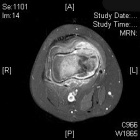

J.S. - 12 year old boy c/o right knee pain and swelling for ten days. Painful at rest, worse at night and with activity. Able to ambulate with pain. Initially the pain was accompanied by fever, chills, malaise, nausea and vomiting; all of which have resolved.